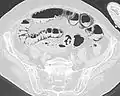

استرواح الأمعاء في التصوير المقطعي الإكليلي في نافذة الرئة. يمكن رؤيته بجوار انحباس الغاز في جدار الأمعاء والغاز في جدار المعدة وفي العديد من الأوعية، بما في ذلك الوريد البابي في الكبد.